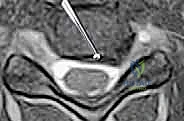

- التصوير بالرنين المغناطيسي (MRI): وهو الفحص الأهم لتحديد موقع الانزلاق الغضروفي بدقة ومدى انضغاط الأعصاب.

- التصوير المقطعي (CT Scan): قد يُطلب للحصول على تفاصيل أدق للتشريح العظمي.

يحدث عندما تتمزق الحلقة الليفية الخارجية للقرص، مما يسمح للمادة الهلامية الداخلية (النواة اللبية) بالبروز والضغط المباشر على العصب الشوكي المجاور أو الحبل الشوكي نفسه.